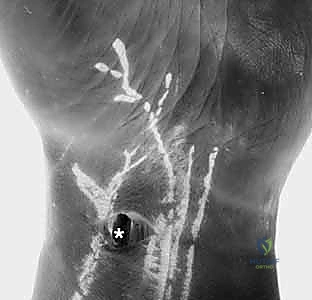

Figure 1B: Arthroscopic view from the VR portal showing a clear DRCL tear ().*

"With our scope now in the VR portal, let's turn our attention to the DRCL. You'll observe the ligament immediately ulnar to the 3-4 portal, just beneath the lunate. We're looking for the characteristic fraying or detachment that signifies a tear."

"Here, you can clearly see the torn edge of the DRCL. It often appears voluminous or frayed, sometimes impinging into the joint space, which can be a source of the patient's pain."

Figure 2B: Arthroscopic view of a DRCL tear from the VR portal. The torn edge is clearly visible.

"Use the hook-probe through the 4-5 portal to palpate the torn edge. Assess its mobility, the quality of the tissue, and the extent of the tear. Is it avulsed from Lister's tubercle, or is there a mid-substance tear? This assessment guides our repair strategy. If there's significant fraying or hypertrophic tissue, use the motorized shaver or suction punch forceps through the 4-5 portal to gently debride the edges, creating a fresh, bleeding surface for optimal healing. Be conservative with debridement; we want to preserve as much ligamentous tissue as possible."